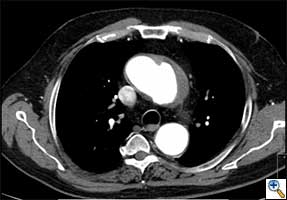

| FIGURE 1-3: 2D and 3D preoperative CT Images of a 78 year old man with aortic insufficiency, and ascending, arch and descending aortic aneurysm with mural thrombus. | |

Appropriate patients for this procedure have extensive thoracic aortic disease and a suitable landing zone for a stent graft in the descending aorta. Many of these patients are candidates for a 2-stage procedure, and selection is based on expected outcomes and the estimated interval rupture risk if patients were to be treated in a staged fashion. (see Figs. 1-3)